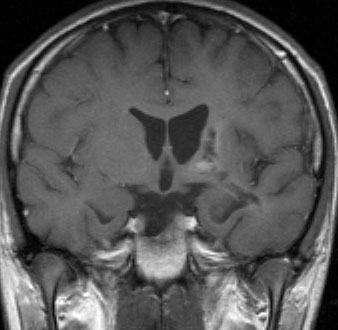

germinomaの視床浸潤:ミッキーマウスの耳

松果体ジャーミノーマは両側視床に浸潤して視床浮腫を生じます。真ん中に第3脳室後半部の割れ目が残っているのが特徴的な所見です。ミッキーマウスの耳みたいになります。かなり特異的な所見であり診断に有用です。右下は治療後です。